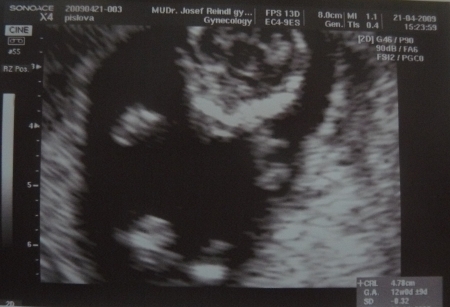

4. Jak vypadá miminko 12. týden těhotenství?

Plod měří na konci tohoto týdne od temene k zadečku asi 6cm, váží asi 10-13q.

Plod stáří 11+2 týdne a velikosti 47 mm. Je vidět hlava s nosem, jasnější horní a dolní čelistí. Vpravo pak dolní končetiny.